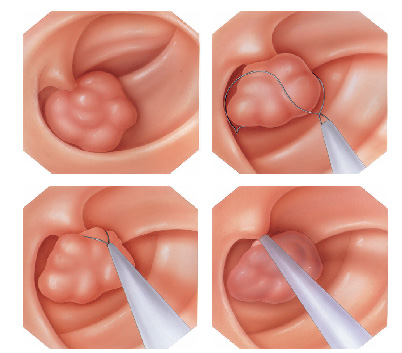

Mucosectomia é o procedimento realizado quando há necessidade de retirada de lesões maiores do trato gastrointestinal.

O exame de Mucosectomia é realizado através de injeção de liquido embaixo da lesão, através de uma agulha específica. Com isso a lesão se destaca das camadas mais profundas do intestino, diminuindo o risco de perfuração.

A retirada da lesão é feita com uma alça de polipectomia e o material é encaminhado para estudo anatomopatológico (no microscópio) da mesma forma que ocorre nas biópsias.

O que é a polipectomia?

A polipectomia é a remoção completa de um pólipo permitindo assim o diagnóstico exato e muitas vezes a cura do próprio problema. Existem várias técnicas para a realização do procedimento que dependem do tamanho e do tipo de pólipo a ser ressecado.

Polipectomia com pinça

Pequenos pólipos podem ser removidos com segurança usando-se apenas uma pinça.

Polipectomia com alça diatérmica

Pólipos maiores necessitam ser removidos com alça e corrente de cauterização. Este procedimento permite cortar a base do pólipo e ao mesmo tempo coagular o local para evitar sangramentos.

Porém alguns pólipos possuem a base (pedículo) largo onde passam vasos calibrosos e por isto tem risco aumentado de sangramento na retirada mesmo usando a corrente de coagulação.

Nestes casos algumas medidas podem ser realizadas para diminuir o risco de sangramento:

Injeção de adrenalina na base do pólipo

Colocação de um laço na base do pólipo para estrangular o pedículo

Alguns pólipos são tão grandes que não podem ser removidos inteiros. Nestes casos o pólipo é retirado em pedaços para poder garantir a sua remoção completa.

Alguns pólipos não possuem a base alongada (pedículo), estes são chamados de pólipos sésseis. A remoção destes pólipos possui risco maior de perfuração do órgão pois como são planos ficam muito próximos da parede externa do órgão.

Mucosectomia

Para diminuir este risco, injeta-se com um uma agulha uma solução abaixo do pólipo para que ele levante e fique mais longe da parede do órgão. Após isto passa-se a alça diatérmica e realiza-se o

procedimento de polipectomia.